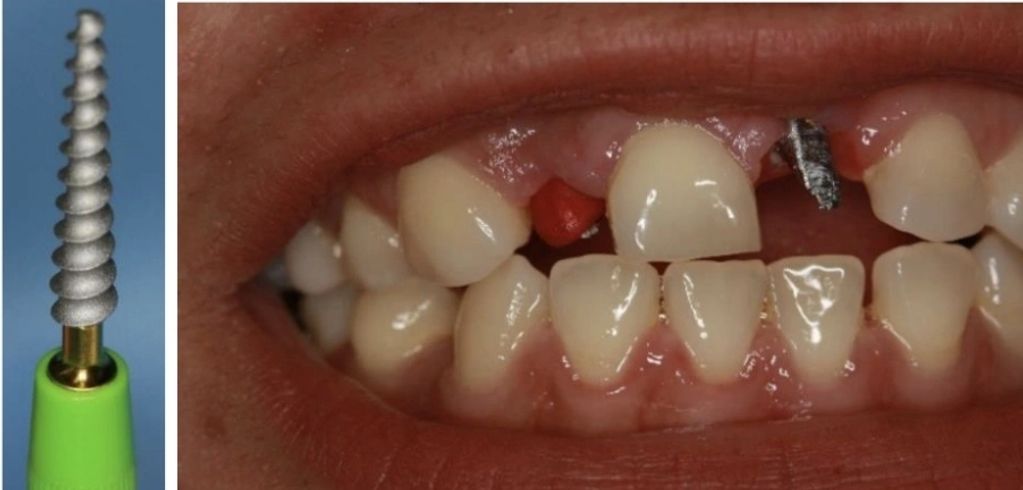

Observamos la foto inmediatamente al finalizar el procedimiento en el cual posicionamos 2 implantes corticobasales estratégicos mediante una cirugía minimamente invasiva, sin levantar colgajos de encía.